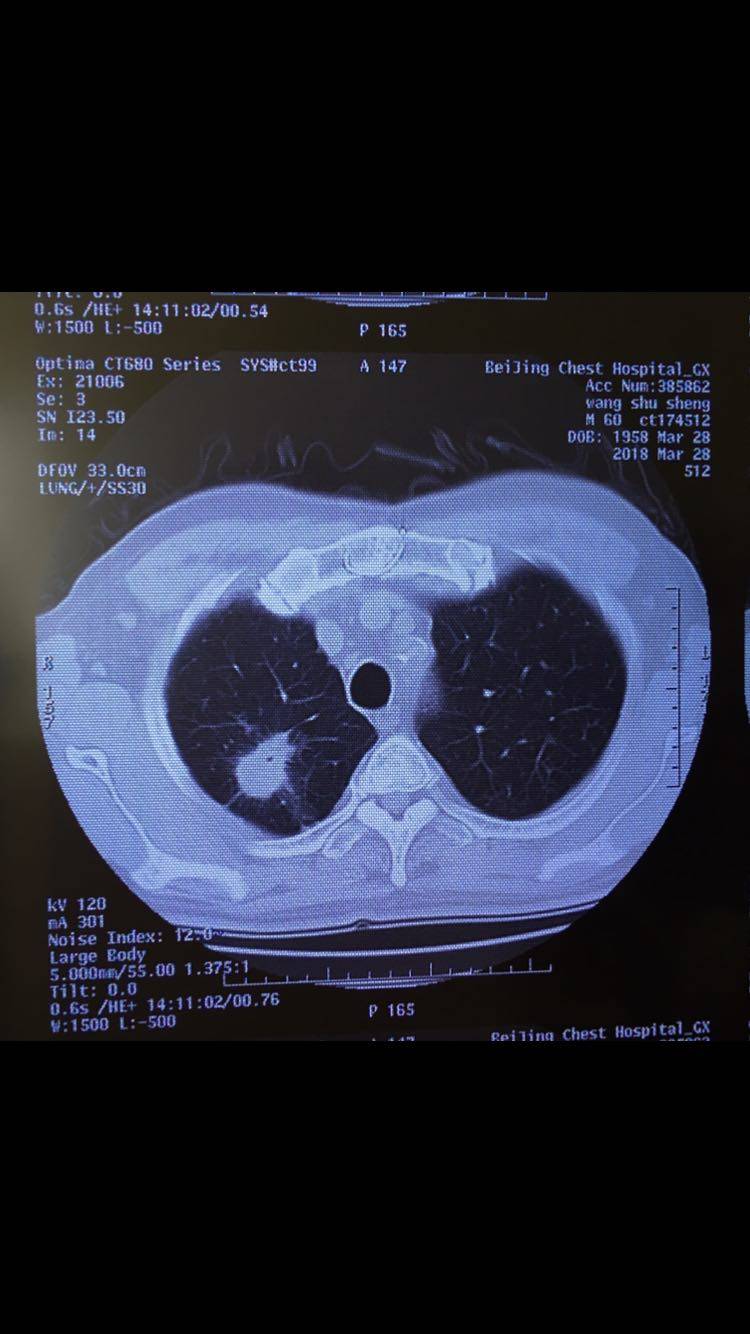

各位病友大家好,相求助听取一下大家的建议,目前患者情况很好,患者自今年三月起确诊肺腺癌晚期,目前使用贝伐珠单抗 培美曲塞 奈达铂化疗了5次,这周准备化疗第6次,主治医说想这次加上放疗同步治疗,我很犹豫,不知道如何选择。请大家给予治疗建议。患者基因检测没有靶向药。B超结果没有其他异常。这几次化疗后CT结果有病灶变小。